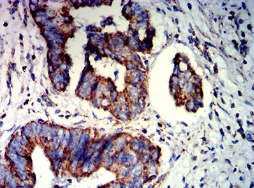

IHC    1/200-1/1000